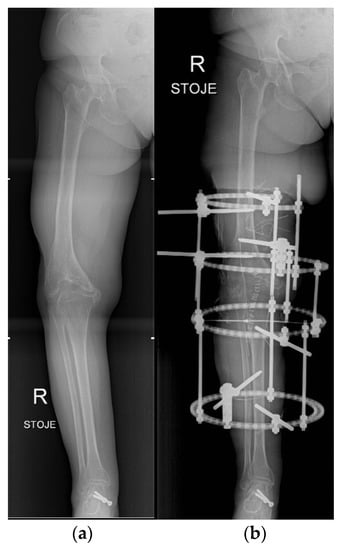

- Brumat, P.; Mihalič, R.; Kovač, S.; Trebše, R. Acute Femoral Lengthening in Adults Using Step-Cut Osteotomy, Traction Table, and Proximal Femoral Locking Plate Fixation: Surgical Technique and Report of Three Cases. Indian J. Orthop. 2022, 56, 559–565. [Google Scholar] [CrossRef]